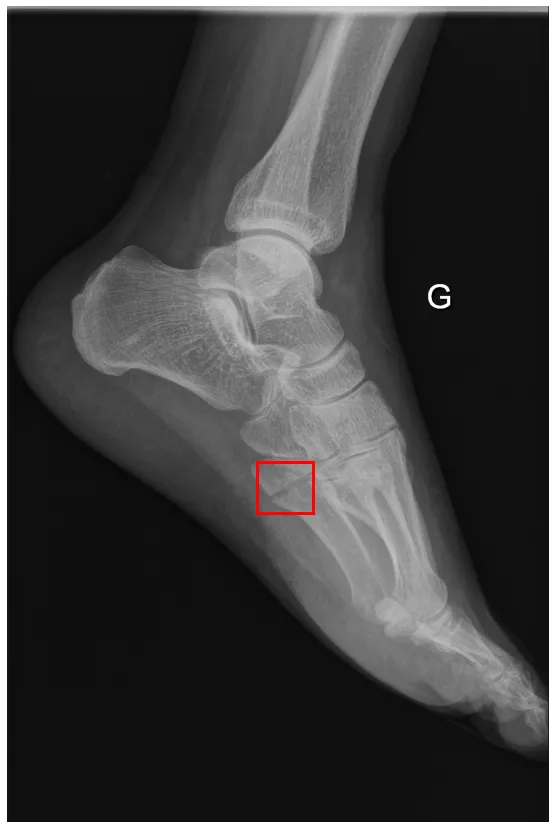

Example of an annotated image (label) Example of an annotated image (with label)

In radiology, we face this problem when we use our algorithms in medical centers different from those on which the training was performed. Over the past two years, we have developed at AZmed a high-performing detection system capable of automatically locating bone fractures on standard radiographs. We started with a state-of-the-art algorithm that excelled at object detection on natural images (i.e., everyday images), and we transformed it to excel at fracture detection on radiographic images.

Our ambition has always been to develop a model that generalizes across all centers. We therefore encountered domain adaptation challenges very early on. This is a real challenge, as we will see later, because each medical center is unique and has its own specificities. Beyond being an exciting challenge for AZmed’s researchers, solving this issue is essential for several reasons. Naively, to get around this problem, one might consider developing a custom algorithm for each medical center using only their own images for training. However, algorithms require thousands of images to achieve the desired performance. This idea would involve a heavy data collection task, followed by an annotation phase involving thousands of images. Indeed, the images provided to the algorithm must be manually labeled beforehand to enable learning. This is a time-consuming task that requires the expertise of several radiologists. Each image in our training dataset must go through the hands of three radiologists: the first writes a medical report, the second annotates the radiograph by drawing a box around the fracture, and the third validates or rejects the annotation.